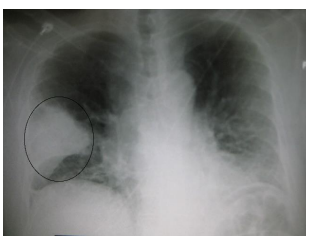

AFC, sexo feminino, 50 anos, portadora de diabetes mellitus não insulino dependente e etilista social, procura atendimento médico se queixando que há 4 dias

iniciou quadro de tosse produtiva, febre de 39,0°C, prostração e dispneia aos médios esforços. Em seu exame físico completo, você verifica crepitações finas em

hemitórax esquerdo e uma taquipneia de 28 IRPM, sem outras alterações relevantes no exame físico. Você solicita uma radiografia de tórax.

Diante do quadro e considerando as principais evidências atuais, entre as alternativas abaixo, qual a MELHOR conduta terapêutica?

Diante do quadro e considerando as principais evidências atuais, entre as alternativas abaixo, qual a MELHOR conduta terapêutica?